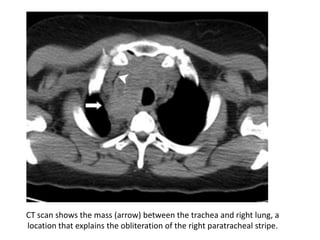

CT scan shows the mass (arrow) between the trachea and right lung, a

location that explains the obliteration of the right paratracheal stripe.